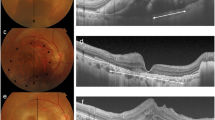

A retrospective analysis was conducted on 18 patients with unilateral vitreous hemorrhage who were treated at our hospital from May 1, 2020 to August 31, 2021. We had access to information that could identify individual participants during or after data collection. Among them, there were 10 male and 8 female patients, aged between 38 and 66 years old, with an average age of 52 ± 0.7 years. None of them had a history of trauma. According to clinical diagnosis (based on ocular ultrasound (Fig. 1), fundus fluorescein angiography, optical coherence tomography, and other relevant examinations), the patients were classified as follows: vitreous hemorrhage with diabetic retinopathy (9 eyes), vitreous hemorrhage with retinal vein occlusion (5 eyes), and vitreous hemorrhage with polypoidal choroidal vasculopathy (4 eyes). Among them, 12 eyes were right eyes and 6 eyes were left eyes, and the visual acuity of all eyes was less than 0.02 in logMAR. There was no history of previous ocular trauma. No vitreous hemorrhage was found in the normal eye, with a naked eye central vision or corrected visual acuity more than 0.8 in logMAR. This study was approved by the Ethics Committee of Fuzong Clinical Medical College of Fujian Medical University with the clinical trial registration number of No. #2020002182 at January 1st, 2020. Written informed consent was obtained from all the patients. Besides, all methods in our study were performed in accordance with the relevant guidelines and regulations.

Typical pictures of the B-scan ultrasonography in eyes without vitreous hemorrhage and eyes with vitreous hemorrhage. An obvious vitreous hemorrhage was shown in the typical pictures of the B-scan ultrasonography in eyes with vitreous hemorrhage, compared to that of the normal eye. N: eyes without vitreous hemorrhage; M: eyes with vitreous hemorrhage; The white arrow: the vitreous hemorrhage.

As showed in the examination of the B-scan ultrasonography, there was an obvious sign of hemorrhage in the vitreous body in the typical pictures of the B-scan ultrasonography in eyes with vitreous hemorrhage. Some parts of hemorrhage were in higher density than the other parts. Meanwhile, the vitreous body was relatively clear in that of the normal eye. No other opacities were found insides the vitreous body (Fig. 1).